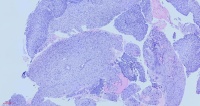

鼻咽肿物

性别年龄59岁临床诊断鼻咽肿物真菌性鼻窦炎

一般病史CT:双侧咽隐窝及咽鼓管开口无变窄,咽鼓管隆突未见增厚,双侧咽旁间隙清晰。左上颌窦内见结节状软组密度影,大小约3.7cm×3.7cm,增强扫扫描呈欠均匀强化,邻近左上颌窦壁见骨质吸收、破坏,部分骨质增厚且密度增高呈骨质硬化改变;左上颌窦内软组织密度影,考虑低度恶性肿瘤与真菌性鼻窦炎鉴别,建议活检;

标本名称鼻腔病损

大体所见灰黄碎组织,质中

免疫组化结果: MDM2(-),CDK4(-),Ki67约60%(+),CD34(-),S100(-),SATB2(+),SMA(-),Desmin(-),P40(上皮+),EGFR(上皮+),CK(上皮+),EMA(上皮+),Vimentin(+)。

癌,没问题。

考虑:鼻咽癌(鳞癌)

鳞癌,非角化型。